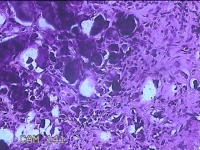

右侧臀部包块

性别

男

年龄

27岁

临床诊断

臀部良性肿瘤

一般病史

发现右侧臀部包块2年余,无明显疼痛及不适。

标本名称

大体所见

灰白暗红色组织2.3x1.7x1.3cm一块,表面带梭形皮肤2x1.3cm,皮下见包块2.3x1.3x1cm一个,切开包块呈实性,切面灰白粉红色,质中。

考虑瘤样钙质沉着,连蒙带猜了。